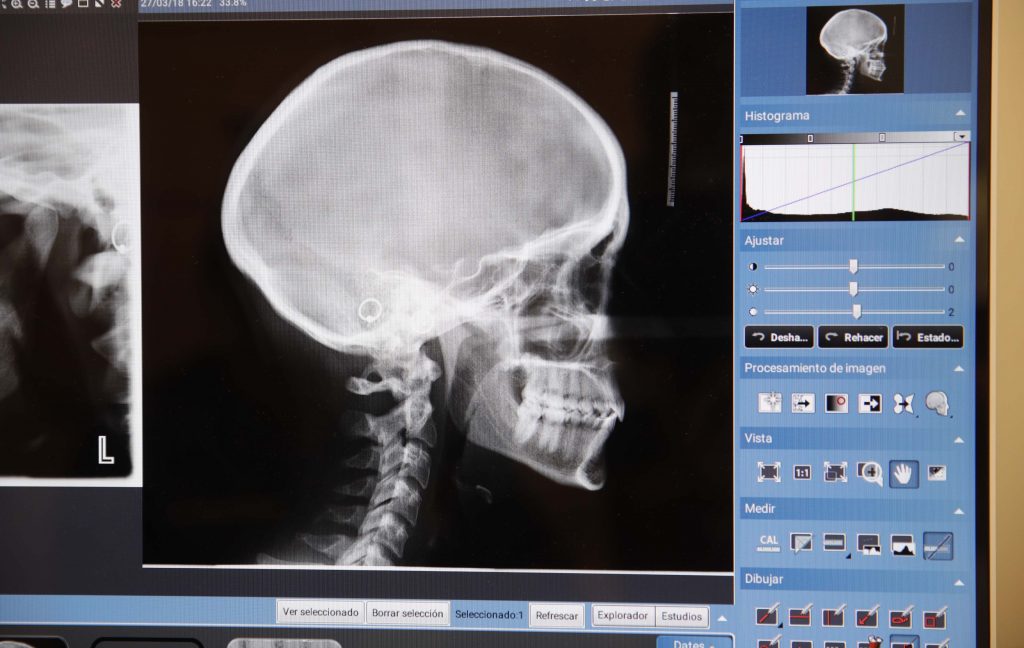

La articulación temporomandibular une la mandíbula con el cráneo, y es la que nos permite masticar y hablar.

Si hay un problema está articulación puede aparecer dolor en la mandíbula, dolor de cabeza, dolor y sobrecarga en músculos del cuello, chasquidos, limitación de apertura de la boca, etc.

En nuestra consulta haremos un estudio y las pruebas necesarias, para intentar comprender el origen del problema y buscar la mejor solución para evitar esos síntomas.